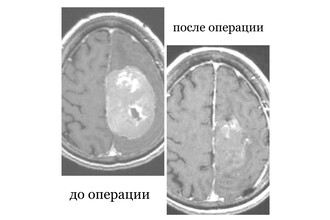

В Бурятии пенсионерка с опухолью мозга шесть лет отказывалась от операции